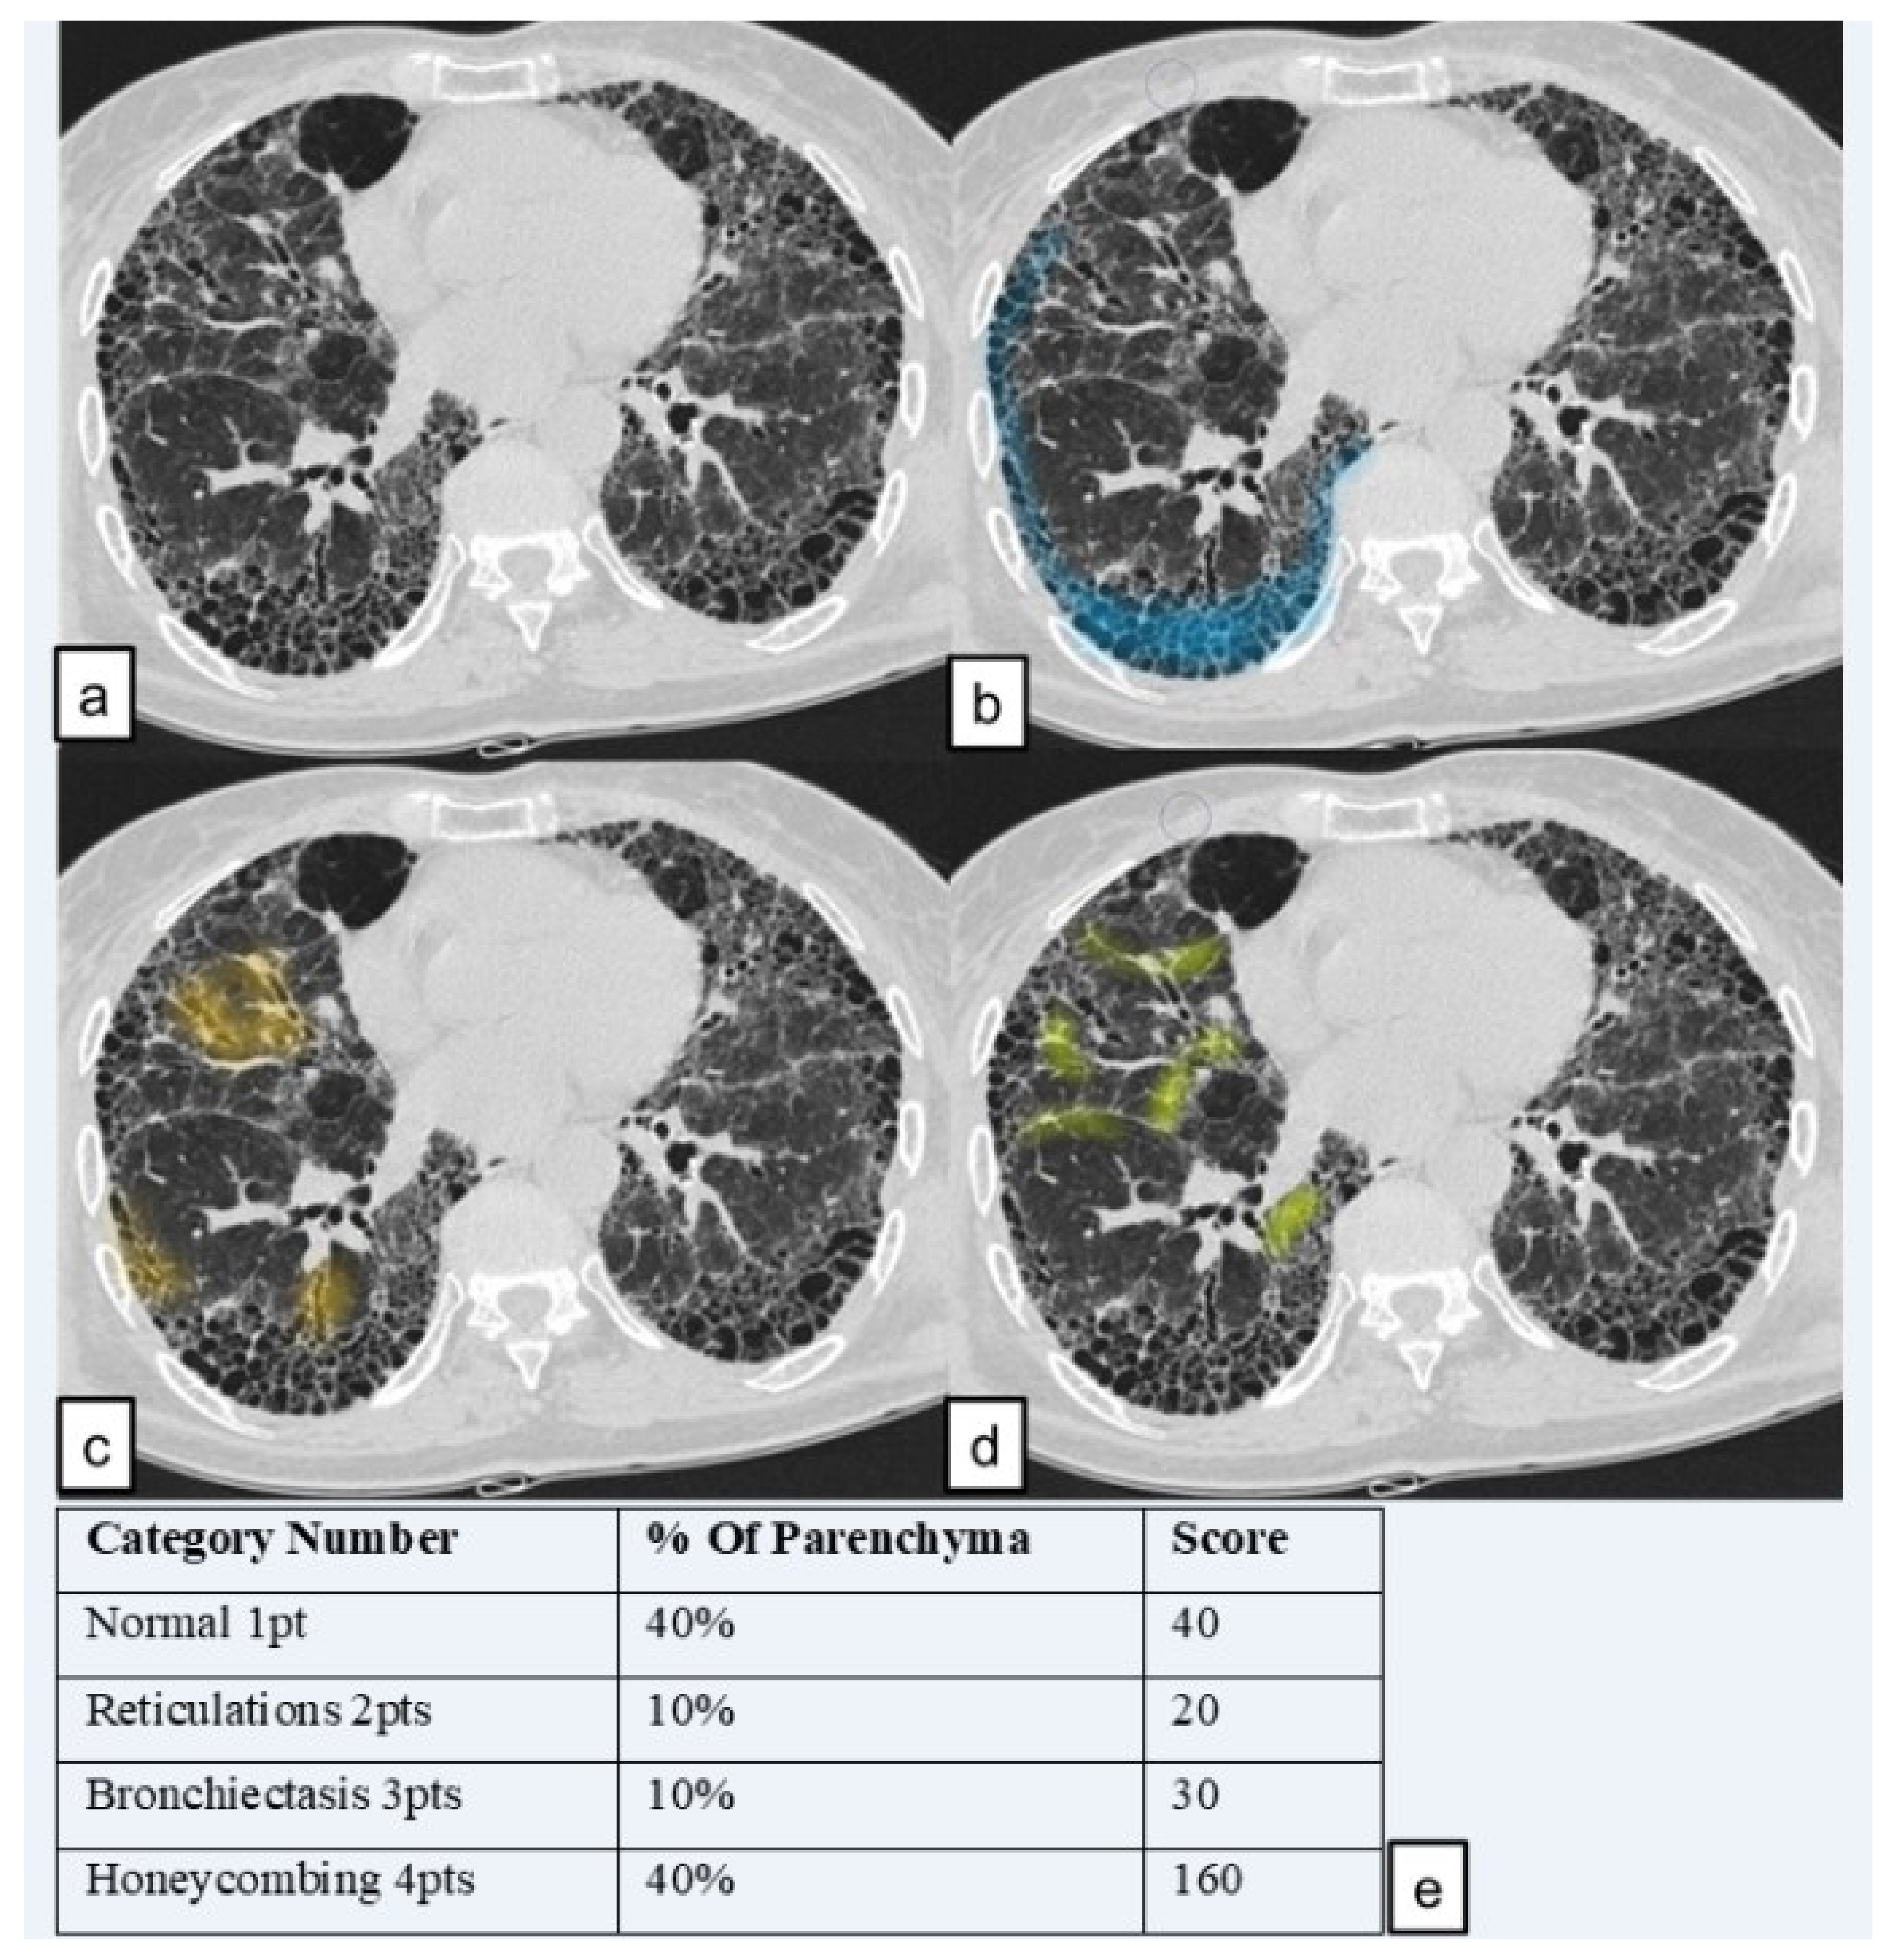

The lung volume of each patient was divided into three different slices (Figure 2):

• “Upper zone”: HRCT slice acquired at the level of carina;

• “Middle zone”: HRCT slice acquired between the carina (“upper zone”) and the level of the inferior pulmonary vein (“lower zone”);

• “Lower zone”: HRCT slice at the area of the lung below the level of the inferior pulmonary vein.

Lung pattern was classified into the four following categories and a grading scale score (1 to 4); each number represents the corresponding category number: (1) normal lung attenuation; (2) reticulations; (3) traction bronchiectasis; (4) honeycombing.

To simplify calculations, we quantified the lung parenchyma in percentage, as proposed by Sánchez et al. in 2018 [20], as represented in Figure 3.

The score for each zone was calculated by multiplying the percentage of the involved area by the grading scale score (1–4). The six zone scores (three zones for the right lung and three for the left one) were averaged to determine the total score for each patient. Using this calculation method, the highest achievable score was of 400 points and the lowest score was of 100 points. The analysis was performed in two steps: in a first “reading analysis”, readers in a blinded mode reported their scores in a worksheet paper of excel; they were blinded for their respective reports. In the second step, they revised, in consensus, their scores. When reports were different among readers, a further evaluation was needed in order to reach, in consensus, a final score.

We named the total score the “HRCT fibrosis score”. An example of how an HRCT fibrosis score was performed (in lower zone of right lung) is provided in Figure 4.

Figure 2. The three zones of high resolution computed tomography (HRCT) visual score. (a) “upper zone”, slice at the level of carina; (b) “middle zone”; (c) “lower zone” slice at the level of the inferior pulmonary vein.

Figure 4. An example of HRCT score of “lower zone” of the right lung. (a) Slice of “lower zone” (b) in blue, area of honeycombing (c) in orange, area with traction bronchiectasis; (d) area of reticulation. (e) Scores of the slice (obtained by multiplying the category number with the affected percentage area).